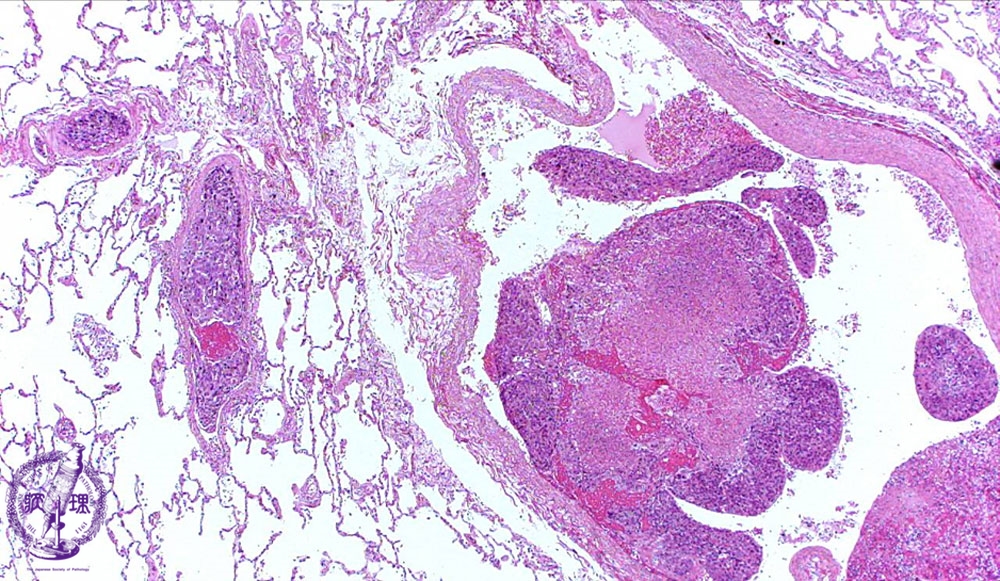

転移性肺腫瘍ミクロ像(HE弱拡大)

ミクロ像(HE弱拡大):肺の血管内に腫瘍塞栓(矢印)を認める。大きな胞巣では中央部に壊死(点線)を伴っている。